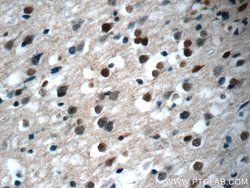

| Applications | Immunohistochemistry (Paraffin), Western Blot |

This KIAA0087 antibody gives a 40 kDa band in Western Blot.

KIAA0087 (KIAA0087 LncRNA) is an RNA Gene, and is affiliated with the non-coding RNA class. Diseases associated with KIAA0087 include Endometrial Cancer and Pancreatic Cancer.Specifications